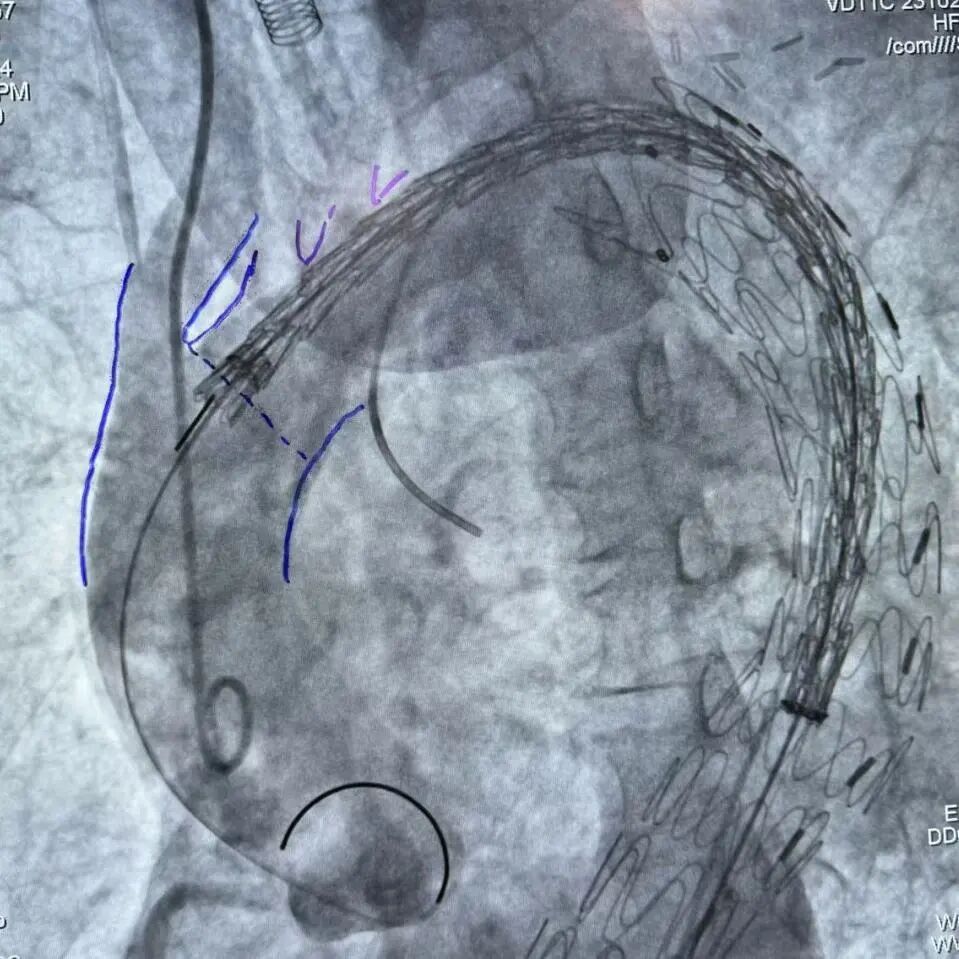

6.再送入Pigtail导管胸主动脉造影:主动脉弓见一巨大瘤样突出,降主动脉见2处瘤样扩张,与CT一致。

gore医疗怎么样「胸有乾坤」可调可控 从容不迫——GORE® TAG® 可主动调控胸主动脉覆膜支架治疗巨大胸主动脉瘤病例报道_https://www.jmylbn.com_新闻资讯_第17张

7.更换GORE® DrySeal亲水涂层导引鞘 DSF2233,送入唯强胸主动脉覆膜支架(DM-TC-3024200)至主动脉弓处,远端准确定位于腹腔干动脉上缘后释放。

gore医疗怎么样「胸有乾坤」可调可控 从容不迫——GORE® TAG® 可主动调控胸主动脉覆膜支架治疗巨大胸主动脉瘤病例报道_https://www.jmylbn.com_新闻资讯_第18张

gore医疗怎么样「胸有乾坤」可调可控 从容不迫——GORE® TAG® 可主动调控胸主动脉覆膜支架治疗巨大胸主动脉瘤病例报道_https://www.jmylbn.com_新闻资讯_第19张

9.送入CADS支架TGM343420至主动脉弓,MPA导管送至升主动脉瘤体处(备弹簧圈和胶体),造影确认CADS准确定位于INA后缘。

gore医疗怎么样「胸有乾坤」可调可控 从容不迫——GORE® TAG® 可主动调控胸主动脉覆膜支架治疗巨大胸主动脉瘤病例报道_https://www.jmylbn.com_新闻资讯_第23张

gore医疗怎么样「胸有乾坤」可调可控 从容不迫——GORE® TAG® 可主动调控胸主动脉覆膜支架治疗巨大胸主动脉瘤病例报道_https://www.jmylbn.com_新闻资讯_第24张

CADS第一步释放,支架从近段向远端打开,释放至50%直径,造影确认调整支架近端位置,精准定位于INA远端。

gore医疗怎么样「胸有乾坤」可调可控 从容不迫——GORE® TAG® 可主动调控胸主动脉覆膜支架治疗巨大胸主动脉瘤病例报道_https://www.jmylbn.com_新闻资讯_第25张

gore医疗怎么样「胸有乾坤」可调可控 从容不迫——GORE® TAG® 可主动调控胸主动脉覆膜支架治疗巨大胸主动脉瘤病例报道_https://www.jmylbn.com_新闻资讯_第26张

CADS第二步释放,支架从远端向近端打开,释放至全直径;随后可以选择性调整近端成角,优化小弯侧贴壁。

gore医疗怎么样「胸有乾坤」可调可控 从容不迫——GORE® TAG® 可主动调控胸主动脉覆膜支架治疗巨大胸主动脉瘤病例报道_https://www.jmylbn.com_新闻资讯_第27张

gore医疗怎么样「胸有乾坤」可调可控 从容不迫——GORE® TAG® 可主动调控胸主动脉覆膜支架治疗巨大胸主动脉瘤病例报道_https://www.jmylbn.com_新闻资讯_第28张

9.经MPA导管送入申淇弹簧圈3条和2盒纤维蛋白粘合剂至主动脉弓瘤体内,经TRG导管送入COOK弹簧圈3条栓塞左锁骨下动脉根部。整体造影见胸主动脉支架贴壁良好,未见内漏,双侧颈总动脉、椎动脉、腋动脉显影良好,未受影响。

gore医疗怎么样「胸有乾坤」可调可控 从容不迫——GORE® TAG® 可主动调控胸主动脉覆膜支架治疗巨大胸主动脉瘤病例报道_https://www.jmylbn.com_新闻资讯_第29张

gore医疗怎么样「胸有乾坤」可调可控 从容不迫——GORE® TAG® 可主动调控胸主动脉覆膜支架治疗巨大胸主动脉瘤病例报道_https://www.jmylbn.com_新闻资讯_第30张